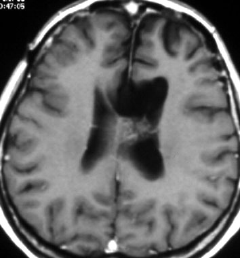

5歳の時に白血病,化学療法と低線量頭蓋照射で治りました。ちゃんと就職して重機の運転をしていましたが,30歳,左足の痙攣で発症しました。多発性髄膜腫が発生していました。摘出する必要があるものです。グレード1の良性の髄膜腫です。